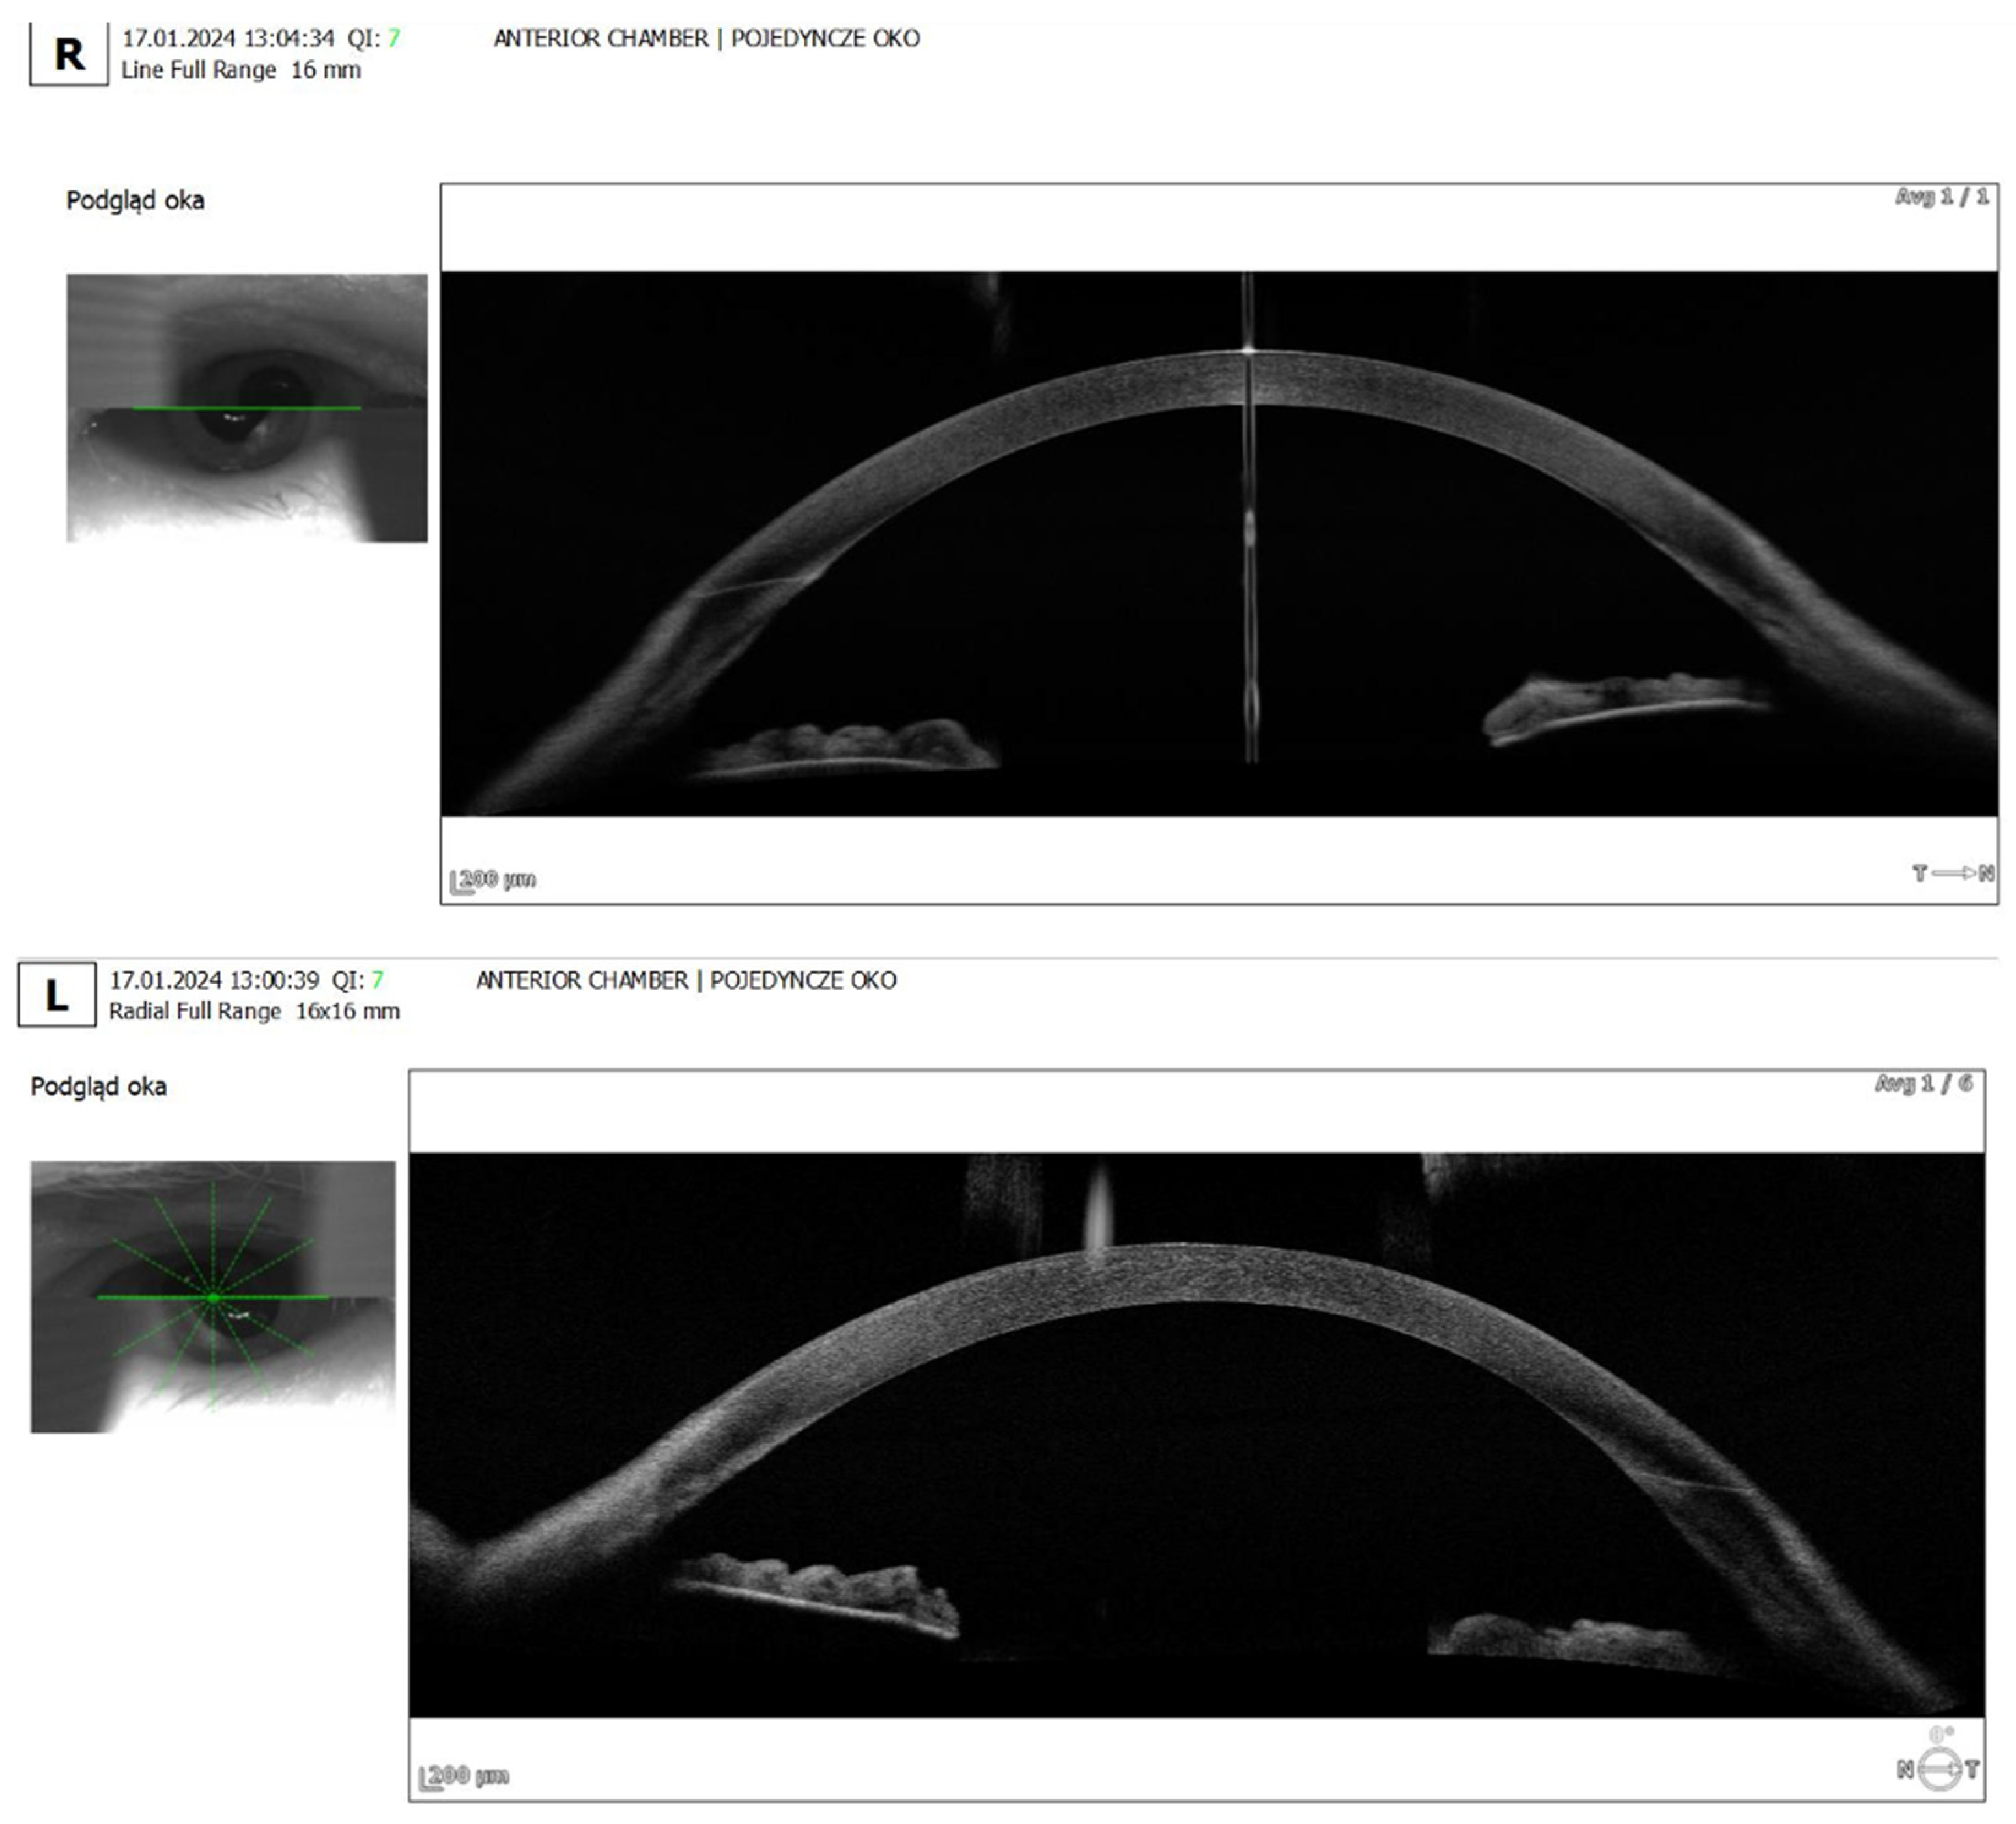

- Anterior segment OCT: Revealed iris plateau configuration, a possible contributing factor to the choroidal effusion (Figure 3).

- A case of 60-year-old male with plateau iris configuration who developed bilateral ciliochoroidal effusion syndrome after acetazolamide use was decribed. The patient presented with a myopic shift, elevated intraocular pressure, and shallow anterior chambers. Upon discontinuation of acetazolamide and the initiation of topical therapy, the choroidal effusion resolved. This case demonstrates how predisposing anatomical factors may contribute to the severity of acetazolamide-induced choroidal detachment [15]

| Anterior Segment | Moderately shallow anterior chambers in both eyes (confirmed on anterior segment OCT) |